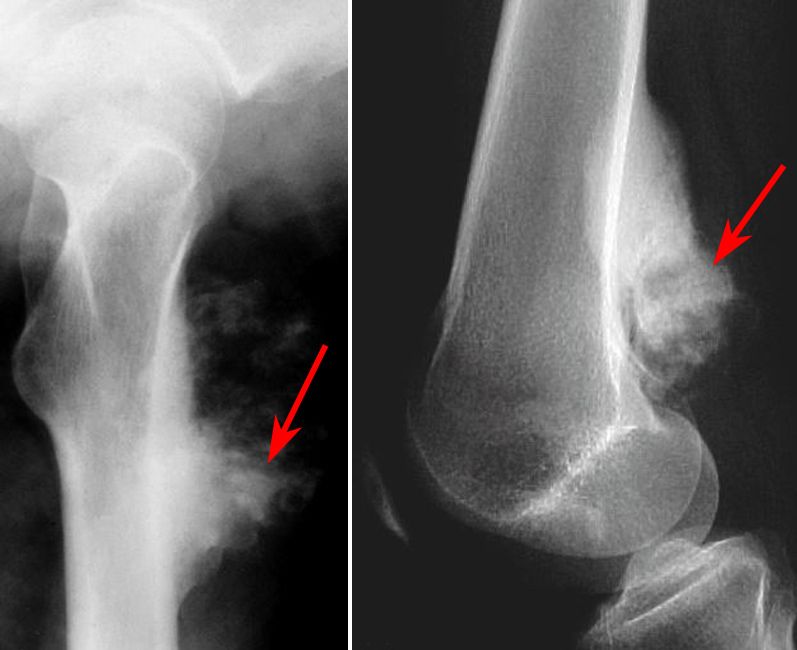

Periosteal and perosteal osteosarcomas

X-rays of two osteosarcoma subtypes. (Left) Periosteal tumors typically occur in the shaft of the tibia (shinbone).  (Right) Periosteal tumors typically occur in the lower femur (thighbone), behind the knee.

Reproduced from Lieberman JR, ed: Comprehensive Orthopaedic Review vol. 1. Rosemont, IL, American Academy of Orthopaedic Surgeons, 2009, p 421.